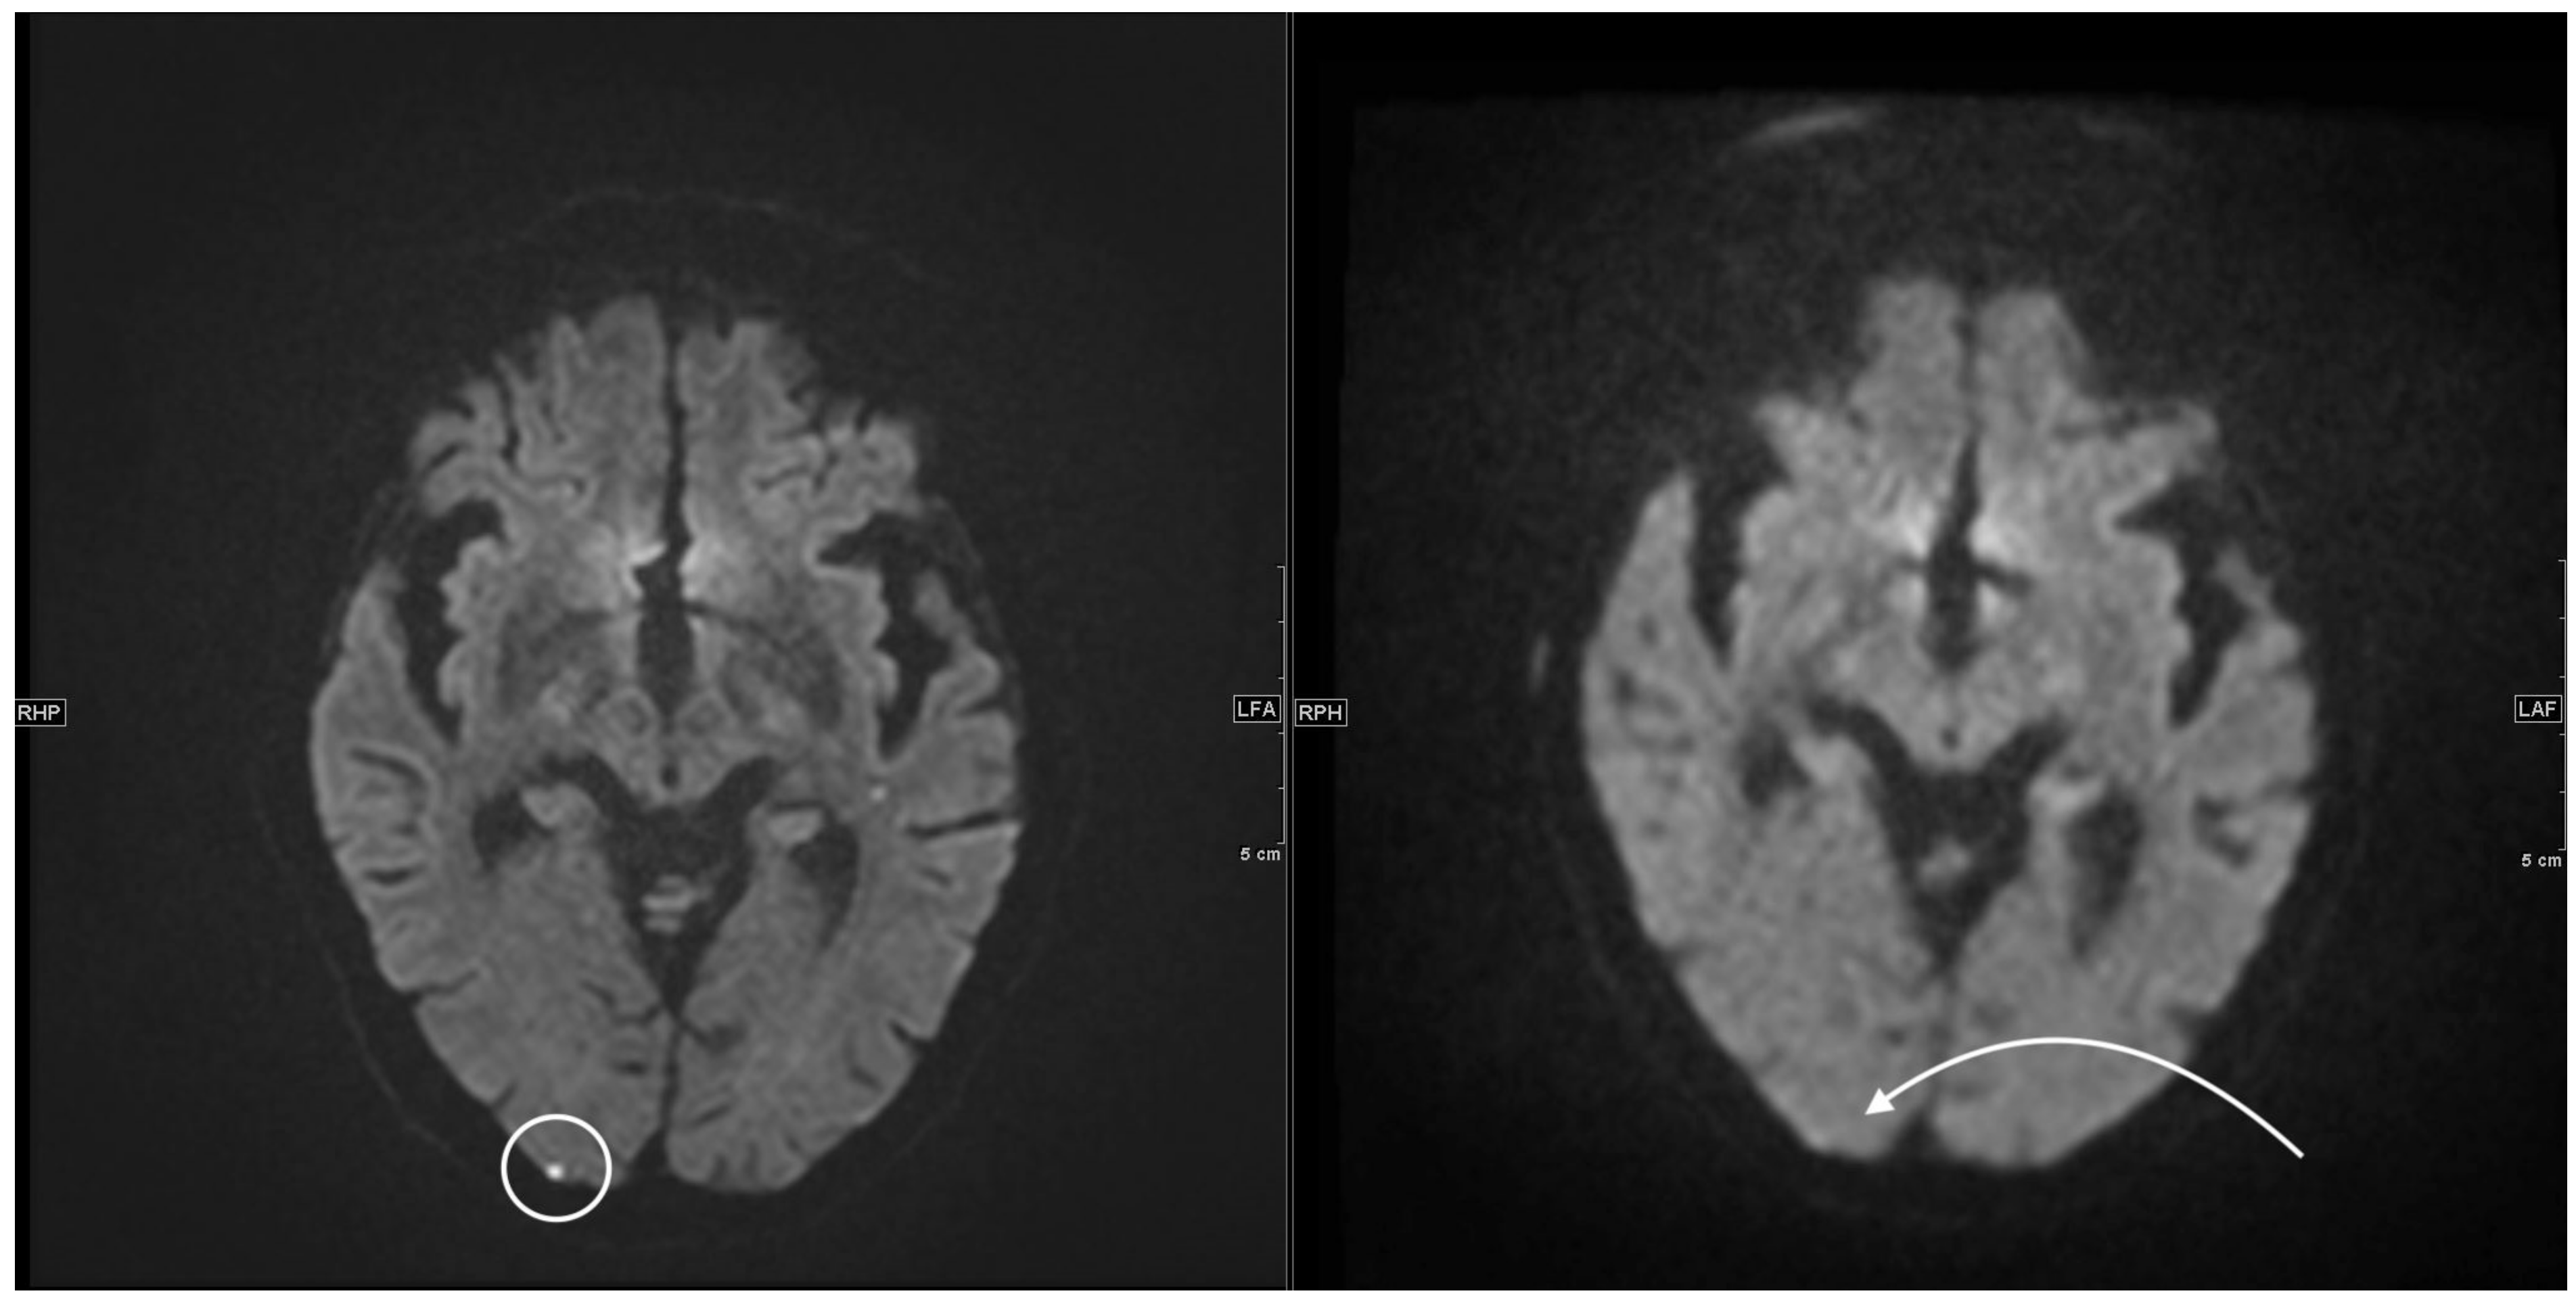

| Patient 5 | 58 | facial droop, hemiparesis right side | 10 | S | multiple subacute infarcts posterior circulation on both sides | 40 | 1050 |